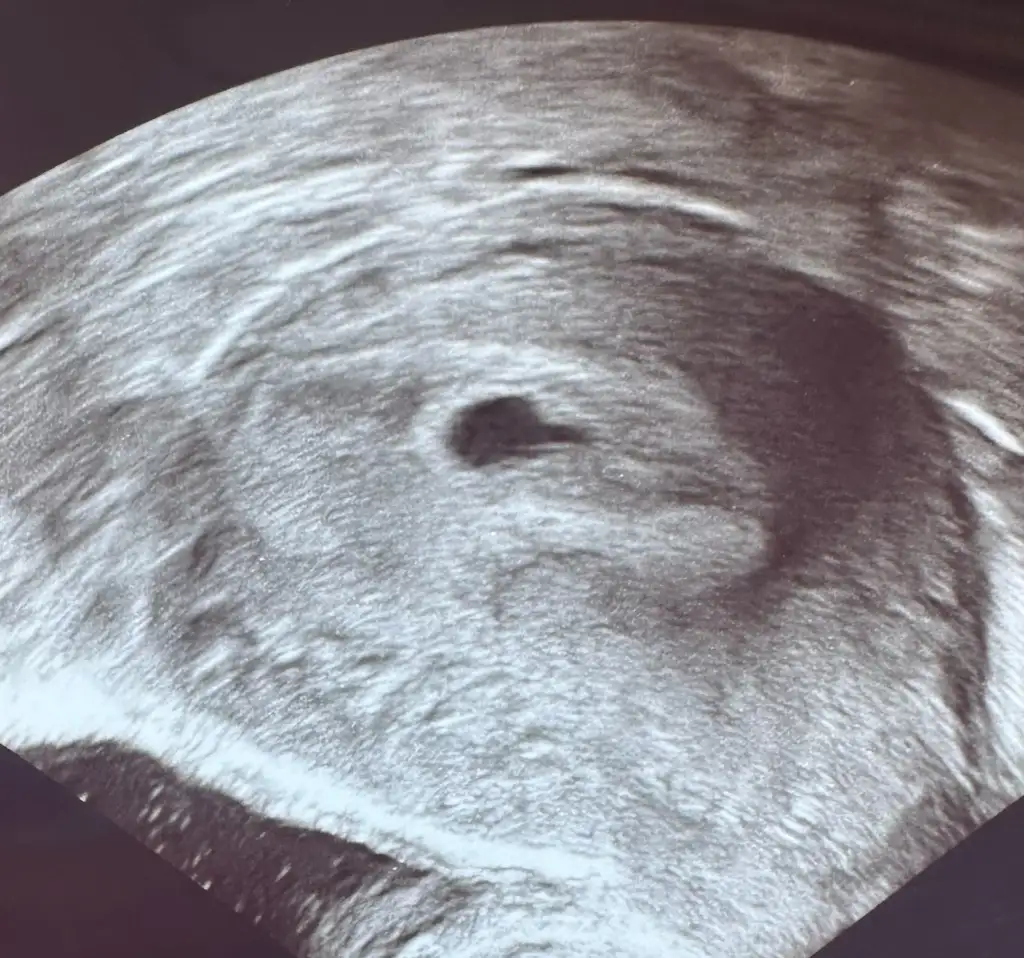

Kızlar betam 5000lerde ama sadece kese gözüktü bugün haftaya tekrar çağırdı doktor kese güzel dedi ama içim hiç rahat değil Eki Görüntüle 3614690

Unutmadan bizde keseyi gördük 2 hafta sonra kalp atışı duymak için tekrar dr gideceğiz

Eklentiler

• IMG_9339.webp

31,8 KB · Görüntüleme: 66